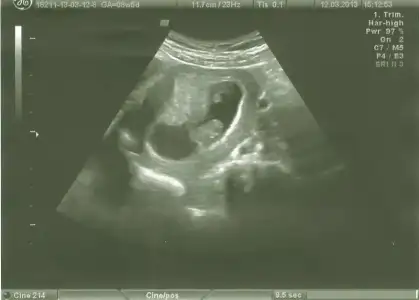

dr soylemeden siz gorun genital nub teorisi ( bebegin cinsiyeti)

teoriye göre bakınca paralelse kız dikse erkek diyoruz ama ben bacaktan hiç ayırd edemiyorum bu nubu yahu...

canım daha erken ama benimkine de bir bakın :1: